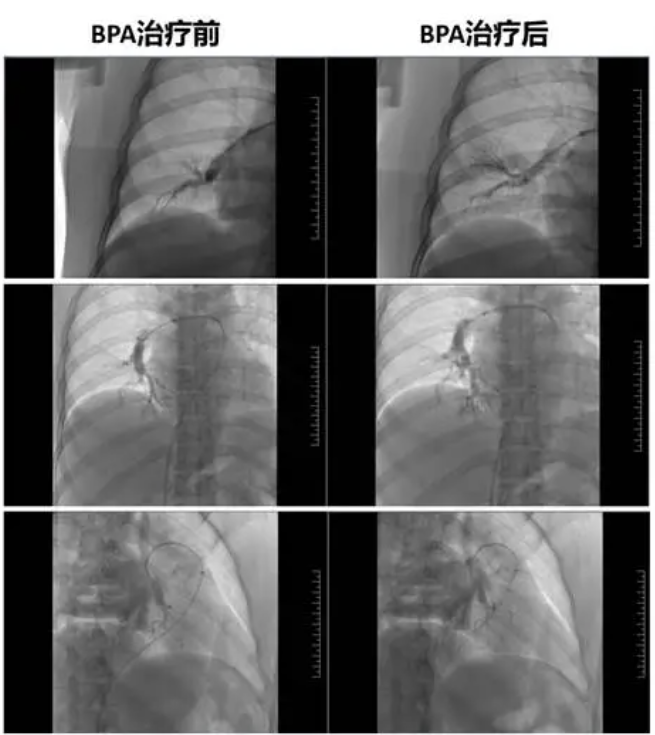

图10 BPA治疗前后肺血流变化

患者贫血改善后,呼吸困难较前明显缓解,可以耐受肺动脉球囊扩张术(BPA)。我们团队先后多次为患者实施BPA治疗,术前术后对比可见肺动脉狭窄、闭塞明显改善(图10),复查心脏超声(图11),患者右心缩小至正常范围,三尖瓣开放正常,患者症状也明显改善,心功能I级,6MWD:432米,可从事正常体力活动。